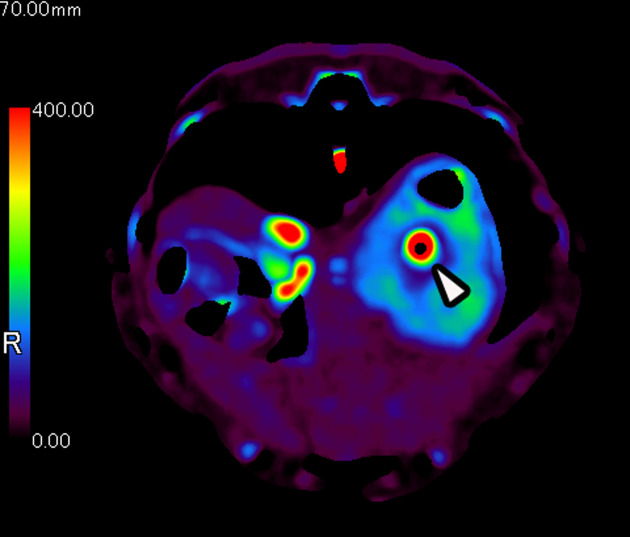

This study aimed to determine the feasibility of using perfusion computed tomography (CT) to assess blood flow in different regions of the stomach in dogs. Dynamic perfusion CT scans were conducted on five beagle dogs, and blood flow analysis was performed using the maximum slope and Patlak plot methods. The findings revealed significant variations in blood flow among the fundus, body, and pylorus of the stomach. Specifically, the body showed approximately 1.3 times higher blood flow than the fundus and approximately 5 times higher blood flow than the pylorus. There were no significant differences in blood flow between the two analysis algorithms. The findings suggest that gastric perfusion CT can accurately detect variations in blood flow within the stomach. Using the maximum slope method for analysis allows for noninvasive and rapid measurement of gastric blood flow. This technique may have clinical applications in detecting submucosal diseases that are challenging to identify with endoscopies and serve as a valuable noninvasive tool for longitudinal observations in experimental animal studies.

Abstract Image